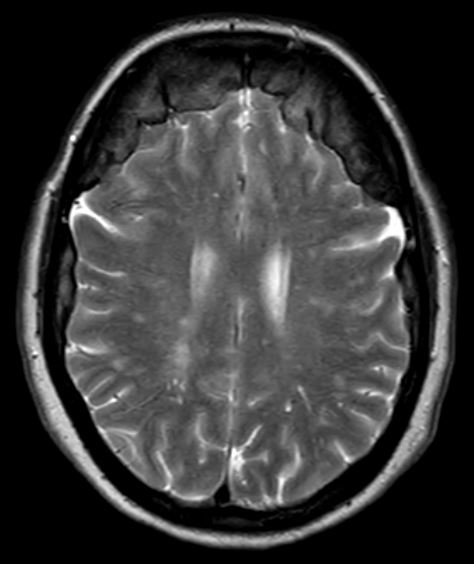

Bifrontale Hyperostose im MRT

Axiale T2 MRT Sequenz einer Patientin mit einer ausgeprägten bifrontalen Hyperostose.